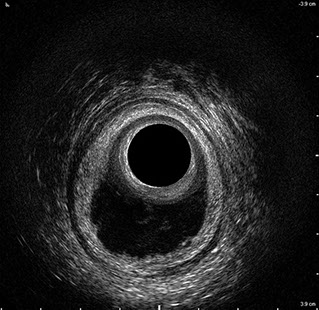

L’ecografia transanale è un esame diagnostico per immagini che consiste nell’introduzione di un trasduttore ad ultrasuoni. Le immagini qualitativamente migliori del canale anale sono ottenute usando un trasduttore rotante, montato in un manipolo rigido, che fornisce un’immagine a 360°. Con le apparecchiature più moderne è anche possibile ottenere immagini tridimensionali.

L’ecografia transanale permette di distinguere la sottomucosa che riveste il canale anale, lo sfintere anale interno, e lo sfintere anale esterno.

Le principali indicazioni all’esecuzione di tale esame sono lo studio dell’integrità delle strutture muscolari nei casi di incontinenza fecale, lo studio topografico dei processi settici perianali (ascessi e fistole) e lo studio dei processi proliferativi epiteliali (carcinoma anale).